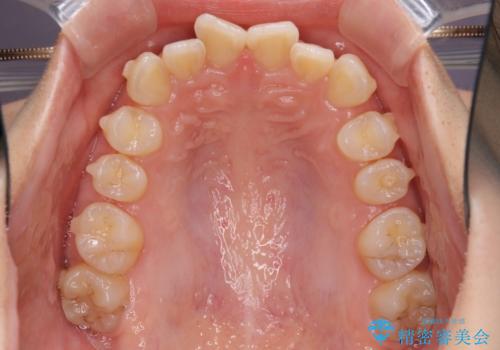

- 口元の深い咬み合わせ(ディープバイト)を気にして来院された患者様です。

インビザラインによる上下歯列の遠心移動(後方移動)により、口元のデコボコとディープバイトを改善することとしました。

下顎左右の犬歯とその後ろにある第一小臼歯、計4歯がシミュレーション通りに動かずディープバイトがなかなか改善されませんでした。

マウスピースの再製作を何度か行いましたがうまくいかないため、部分的にワイヤー矯正を併用することを提案しました。しかし、最も気になっていた前歯のデコボコはきれいに改善されたため、これ以上治療を希望されず、治療を終了することとしました。(今後気になった際には再開する予定です)